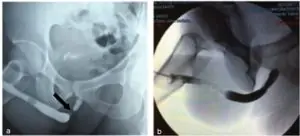

Απεικόνιση 1 Ουρηθρογραφία ασθενούς με στένωμα 1 εκ. στην περιοχή της βολβικής ουρήθρας: (a) πριν τη διαστολή του στενώματος και (b) 6 μήνες μετά τη διαστολή του στενώματος με το μπαλόνι Optilume.

Η ιδιαιτερότητα του μπαλονιού αυτού διαστολής είναι η επικάλυψη των εξωτερικών τοιχωμάτων του μπαλονιού από το δραστικό φαρμακευτικό συστατικό πακλιταξέλη, το οποίο εμφυτεύεται όπως φουσκώνει αυτό κυκλικά σε όλη την επιφάνεια της ουλής. Η κυτταροστατική ιδιότητα της πακλιταξέλης επιτυγχάνει την αναστολή του πολλαπλασιασμού και τη μετανάστευση των λείων μυϊκών κυττάρων και των ινοβλαστών, καθώς και την έκκριση της εξωκυττάριας θεμέλιας ουσίας. Ο συνδυασμός αυτών των επιδράσεων έχει ως αποτέλεσμα την αναστολή της υπερπλασίας του ουροθηλίου και η στένωση δεν επανεμφανίζεται.

Η διαδικασία αυτή διαρκεί περίπου 20 λεπτά υπό καταστολή ή νάρκωση. Ο ασθενής εξέρχεται από το νοσοκομείο την ίδια ημέρα με ένα λεπτό καθετήρα, ο οποίος αφαιρείται 48 ώρες μετά. Τα αποτελέσματα της μεθόδου είναι εξαιρετικά ενθαρρυντικά. Κλινικές μελέτες τριετίας αποδεικνύουν ότι το 77% των ασθενών που επέλεξε το Optilume δεν χρειάστηκαν σε αυτό το διάστημα επανάληψη της ουρηθροτομής ή διαστολών ουρήθρας, διατήρησαν ικανοποιητική ροή ούρων και απαλλάχθηκαν από ένα βαρύτερο χειρουργείο, αυτό της ουρηθροπλαστικής!